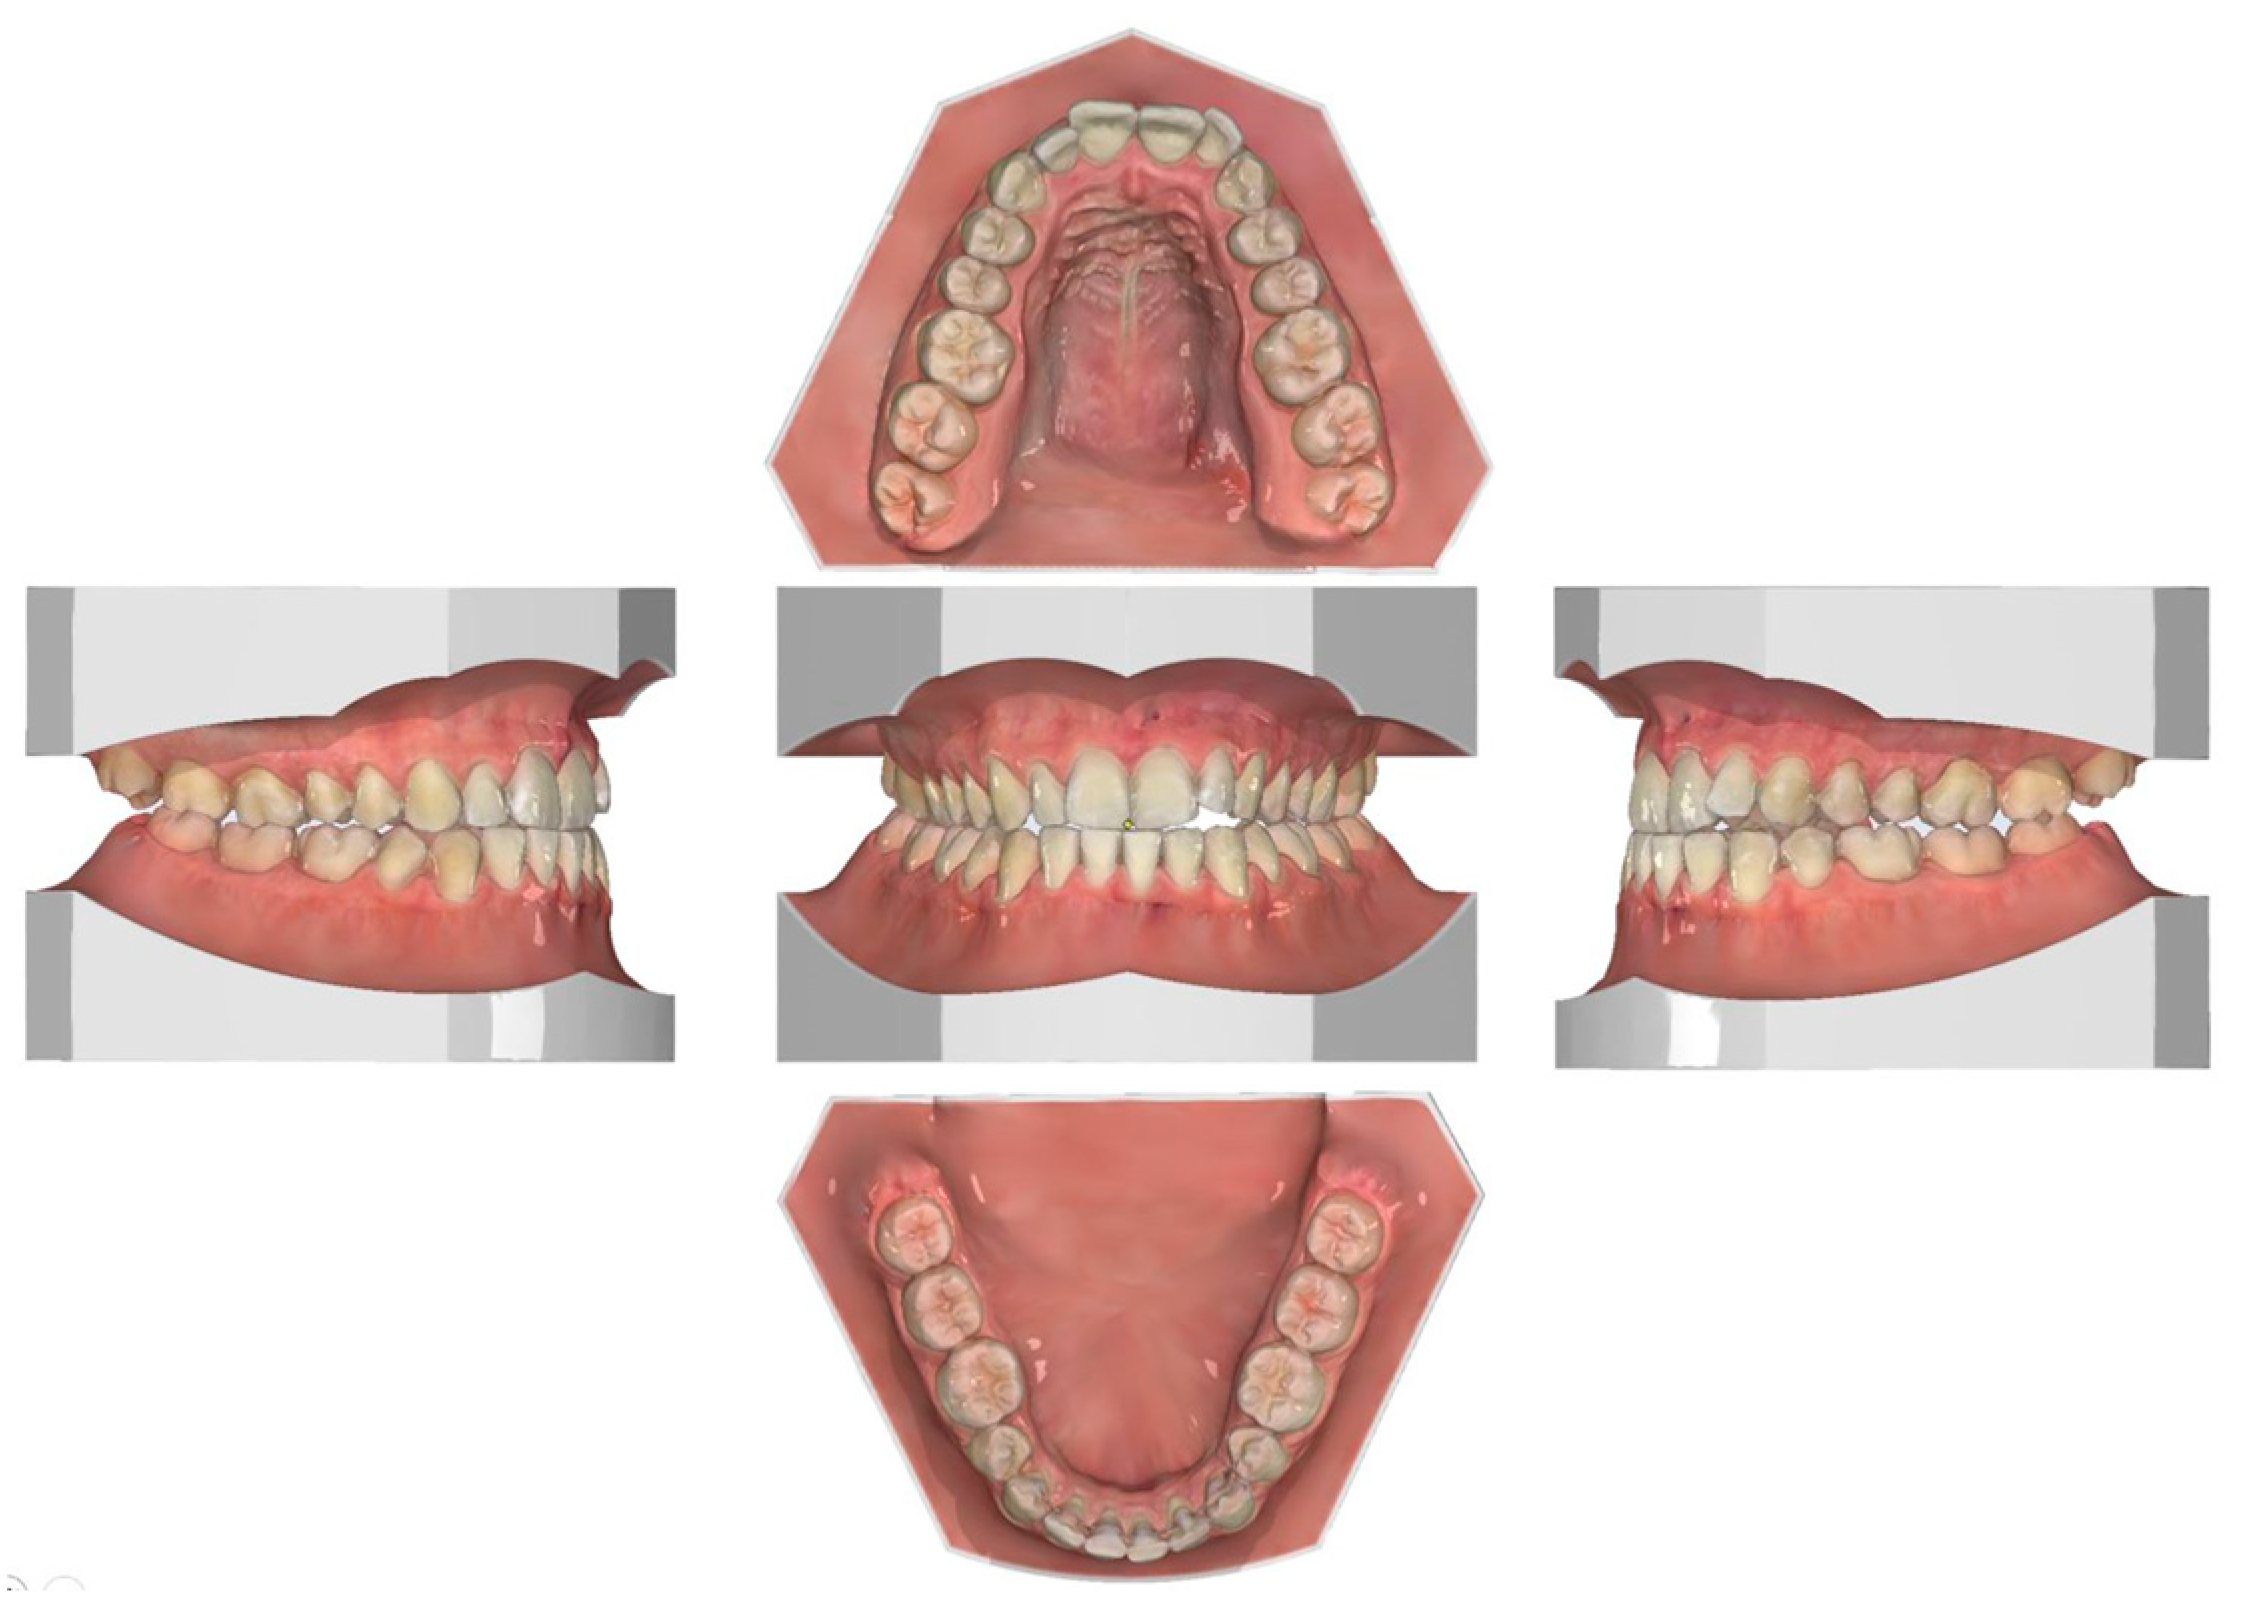

2.2. Clinical Preparations